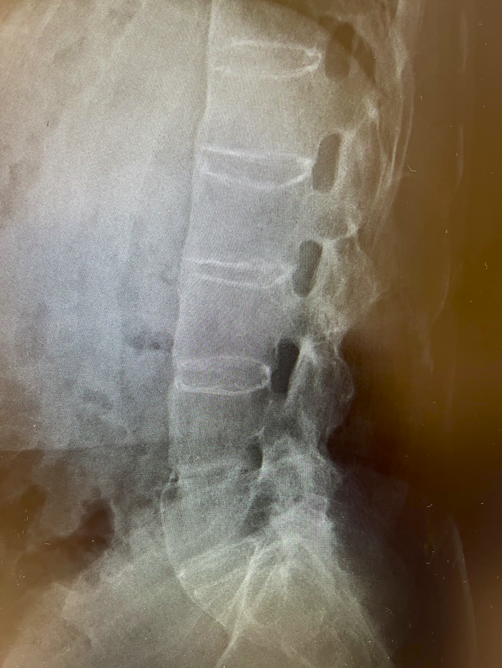

若年男性に発症した、運動により改善して安静により改善しない3か月以上持続する炎症性腰背部痛の所見と血清反応陰性、CRPの上昇より脊椎関節炎を疑った。単純X線では両側仙腸関節に関節裂隙全体の強直を認めgrade4の仙腸関節炎の所見であった(写真1)。また、同写真で腰椎の椎体辺縁に沿った硬化像も認めた(写真1)。追加で行った頸椎(写真2)、胸椎(写真3)、腰椎(写真4)単純X線の側面像では全脊椎の強直(竹様脊椎、bamboo spine)を認めた。以上より強直性脊椎炎と診断した。

写真1 単純X線 骨盤正面像

両側仙腸関節にgrade4(関節裂隙全体の強直)の所見(黄色矢印)と腰椎の椎体辺縁に沿った硬化像を認める(白色矢印)